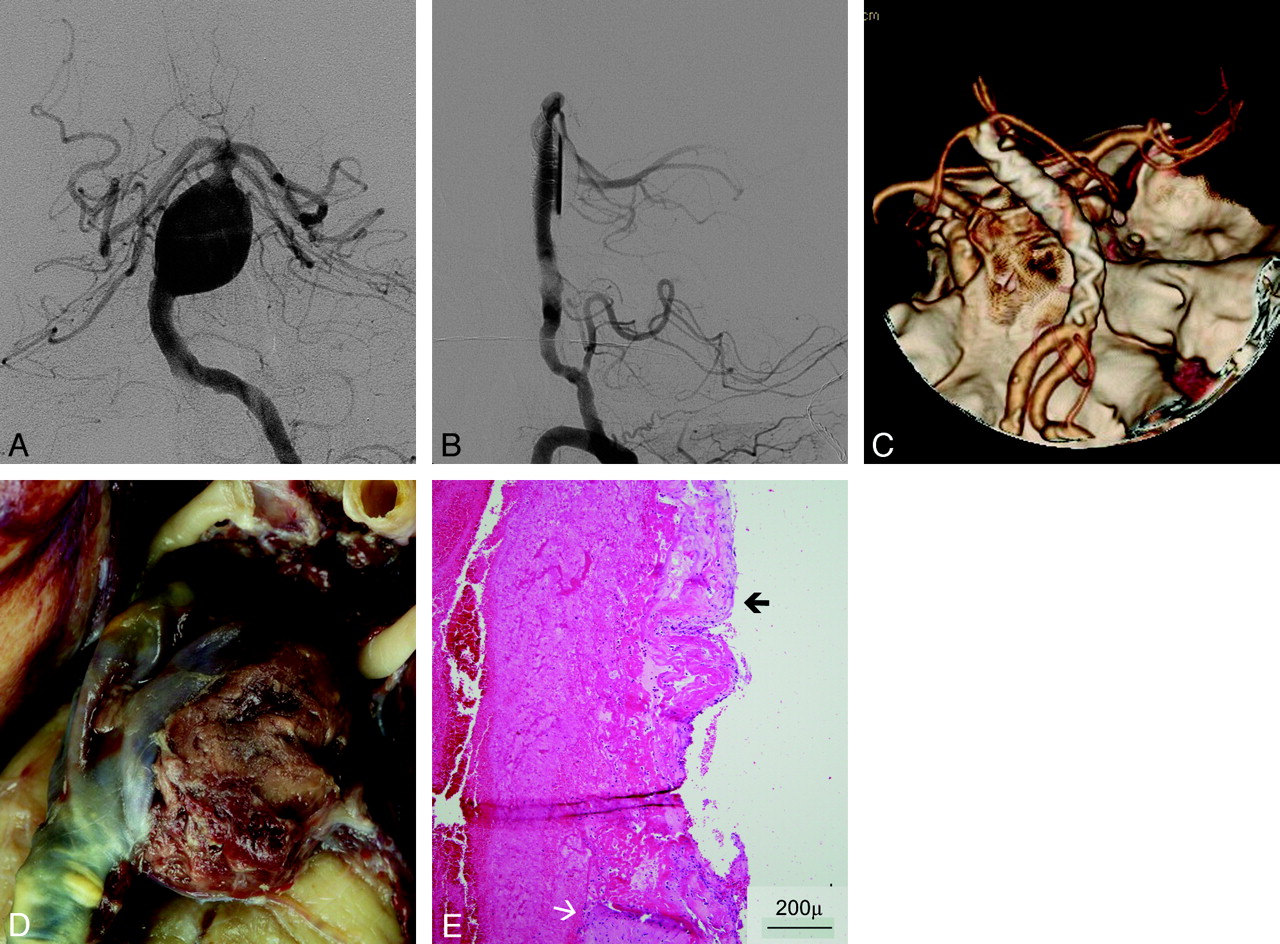

Flow-Pattern Changes after FD Implantation

On the basis of conventional DSA images, an inflow jet was identified before device implantation in 12 of 13 patients. After device implantation, this was still present and clearly identifiable in 11 cases (Fig 1). FD placement increased contrast material stagnation in the aneurysm cavity in all cases.

Patient No. 3. A, Posteroanterior view DSA image of an incidentally discovered left ICA parophthalmic aneurysm. B, Persistence of the inertia-driven inflow jet (arrow) is shown after device deployment. C and D, Nonenhanced CT scan 2 days after intervention shows already partial thrombosis of the aneurysm (C), and a CT angiogram at day 5 shows massive subarachnoid hemorrhage and only a minor portion of the aneurysm that is still perfused, corresponding to the inflow jet area (open arrow) (D).